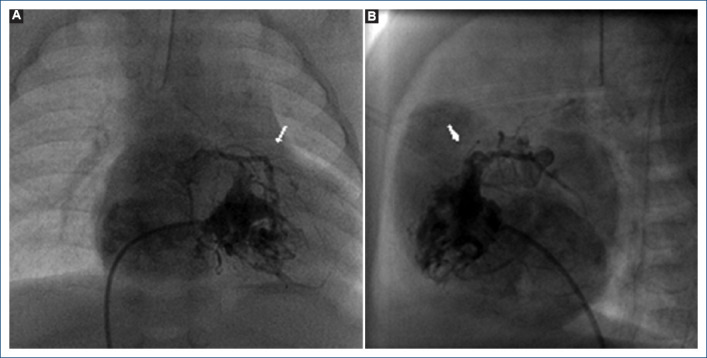

Objective: Pulmonary atresia with intact ventricular septum (PA-IVS) is a rare congenital heart disease characterized by a wide morphological spectrum that can be associated with abnormalities in the coronary circulation such as sinusoids, fistulas, stenosis or atresia. Some patients do not present ventriculo-coronary fistulas or intramyocardial sinusoids, other patients do present ventriculo-coronary connections, but only some of the latter will have right ventricle-dependent coronary circulation (RVDCC); timely establishment of the diagnosis of RVDCC is essential, since the prognosis of these patients is generally fatal. There are reports of patients with this type of coronary circulation (RVDCC) who were undergone to univentricular physiology, but this treatment option remains controversial, so the purpose of this manuscript is to share three cases with PA-IVS and RVDCC, their outcome and the reflections they provide us.

Results: Three patients were identified, the clinical and angiographic characteristics and their evolution are described, and a new technique or maneuver for transient percutaneous decompress of the right ventricle is described theoretically for those cases where there is doubt about RVDCC during the angiographic study.

Conclusions: An accurate diagnosis regarding the existence of RVDCC is vital. In some cases, the interpretation of angiography for the diagnosis of RVDCC can be difficult to pinpoint and in many cases, it can be operator dependent, however we consider that is necessary to have a technique or maneuver that can objectively and without doubts determine RVDCC in those cases where angiography is not totally conclusive and thus be able to offer the best therapeutic option.